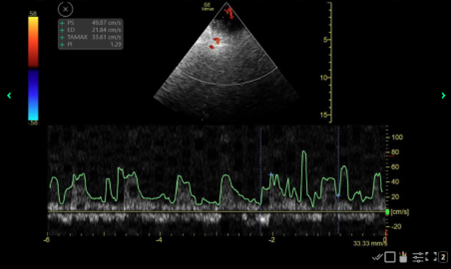

Point-of-care ultrasound (POCUS) using TCD was performed using a high-frequency phase array probe with the patient in the supine position and eyes closed. Ultrasound gel was used over a transparent dressing placed over the eyelid to minimize pressure on the globe. Bilateral ophthalmic arteries (OA) and internal carotid arteries (ICA) were insonated through the closed eyelids in axial plane (Figure 1). Given the patient’s lack of transtemporal windows, MCA velocities could not be measured.

Peak systolic and end-diastolic velocities were measured for both OA and ICA. These values were applied to the IMPRESSIT equation which estimates cerebral perfusion pressure (CPPe) using the MCA diastolic and mean blood flow velocities (FVd and FVm respectively). The CPPe is then used to calculate ICP1,2,3:

CPPe = MAP*FVd /FVm + 14 = 58.8

ICP = MAP - CPP = 69-58 = 11

ICP was also calculated from the pulsatility index as a comparison4:

ICP = (10.93 x PI) - 1.28 = 12.8

These equations yielded an estimated ICP significantly lower than the EVD readings, supporting the hypothesis of inaccurate invasive measurements.

Figure 1: Shown here is a screenshot of the TCD waveform obtained from the left ophthalmic artery. The Mean Flow Velocity (MFV) (denoted by the TAMAX), End Diastolic Velocty (ED), and the Pulsatility Index (PI) from these measurements were used in the appropriate formulas along with a Mean Arterial Pressure (MAP) of 69 that was measured simultaneously to calculate the intracranial pressure (ICP). This is one screenshot, but several were taken (though not pictured) to ensure accuracy and appropriate capture of the measurements.